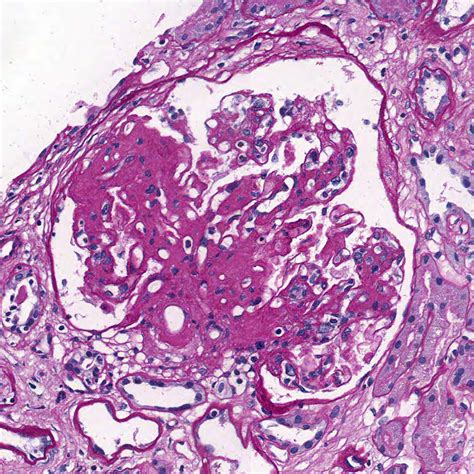

Focal Glomerulosclerosis Kidney Disease is a serious condition characterized by the formation of scar tissue in some, but not all, of the glomeruli in the kidneys. The term "focal" indicates that only a portion of the glomeruli are affected, while "segmental" refers to the fact that only part of an individual glomerulus is scarred. When these filtering units become damaged and scarred, the kidneys begin to leak protein into the urine, a condition known as proteinuria, which is a hallmark sign of the disease.

To confirm a diagnosis of Focal Glomerulosclerosis Kidney Disease, physicians rely on a combination of laboratory tests and imaging. Because the scarring is "focal," the diagnosis requires a microscopic examination of kidney tissue.

Kidney Biopsy Retrieves a small tissue sample to view scarring under a microscope.